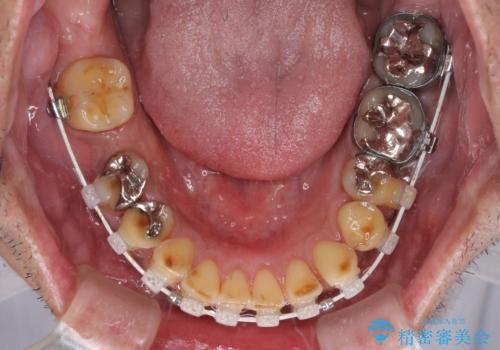

- 矯正装置

- 審美装置

奥歯の欠損が散見されており、銀歯の装着されている歯も多いため、ワイヤー矯正にて歯列を調整し、その後オールセラミッククラウンにて補綴治療を行うこととしました。

矯正治療は想定通り長期化しましたが、しっかりと奥歯の咬み合わせを向上させて前歯の被蓋を改善させることができました。